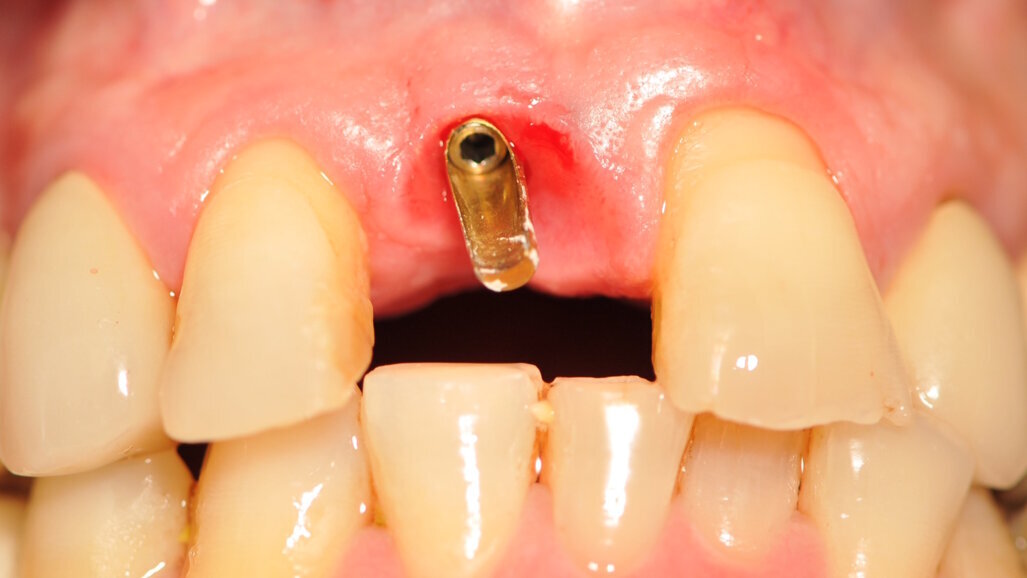

Paziente di sesso maschile di 60 anni di età giunto alla nostra osservazione per una edentulia parziale dovuta all’assenza dell’elemento 1,1. La situazione clinica è resa esteticamente e funzionalmente complicata dalla assenza dell’elemento 2,2 che considerato lo spostamento dei denti contigui comporta un aumentato spazio per la sostituzione protesica dell’elemento 1.1. Si effettua dopo rx di controllo il posizionamento di un impianto osteintegrato GTB diametro 3,6 x 9 mm ,con posizionamento, come da protocollo, 1,5 mm sottocrestale ed inserzione immediata di moncone easy abutment slim 3,4 x 7 mm altezza gengivale 3,5 mm. angolato a 10 gradi (Easy Abutment Slim – GTB Plan1Health Amaro, UD, Italy). Con l’ausilio di una cappetta easy si costruisce e si cementa, con tecnica extraorale, una corona provvisoria in resina acrilica con forma a pontic su elemento 1.1 in modo da eseguire un carico immediato e fornire al paziente una estetica immediata (Figg. 1-3). Dopo 12 settimane ad avvenuta osteointegrazione si provvede all’impronta definitiva eseguita a livello abutment con elastomero di precisione Aquasyl Monophase (Dentsply) e con idonea cappetta easy (GTB Plan1Health Amaro, UD, Italy). La stessa cappetta easy viene utilizzata dal laboratorio odontotecnico come cappetta da sovrafusione garantendo standard di precisione stabiliti industrialmente (Figg. 4-8). La corona costruita in lega preziosa e porcellana viene cementata dopo una settimana, fatte le prove estetiche e occlusali necessarie sul paziente. I controlli a distanza di 4 anni, sia radiografici che clinici, confermano la stabilità dell’osso intorno all’impianto e la mancanza di perdita di tessuto gengivale attorno allo stesso (Figg. 9-11).

Fig. 5_Moncone Easy slim angolato, notare la quantità di tessuto cheratinizzato dopo condizionamento funzionale con corona provvisoria a pontic.